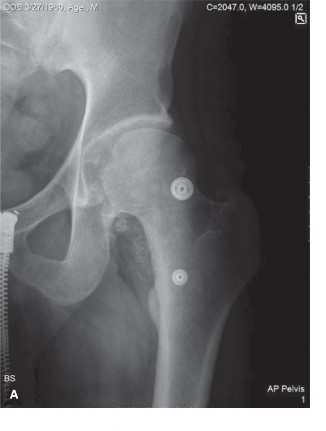

Plain Radiography Findings

Initial radiographs of the right knee, including anteroposterior, lateral, skyline, and weight-bearing views, demonstrated multiple, well-circumscribed, oval or curvilinear radiopacities within the joint space, varying in size from a few millimeters to approximately 1.5 cm. These calcified loose bodies were most concentrated in the suprapatellar pouch, the medial and lateral gutters, and the posterior recesses of the knee.

The radiographic pattern exhibited the classic "ring-and-arc" chondroid mineralization, pathognomonic for hyaline cartilage matrices that have undergone endochondral ossification. Importantly, the underlying joint space was relatively preserved, with minimal osteophyte formation or subchondral sclerosis. This lack of advanced degenerative joint disease is a critical radiographic differentiator, suggesting that the loose bodies are the primary pathology (Primary Synovial Chondromatosis) rather than secondary osteochondral fragments resulting from advanced osteoarthritis or neuropathic arthropathy. Extrinsic scalloping of the anterior femoral cortex was noted, a secondary sign of chronic pressure erosion from the hyperplastic synovial masses.